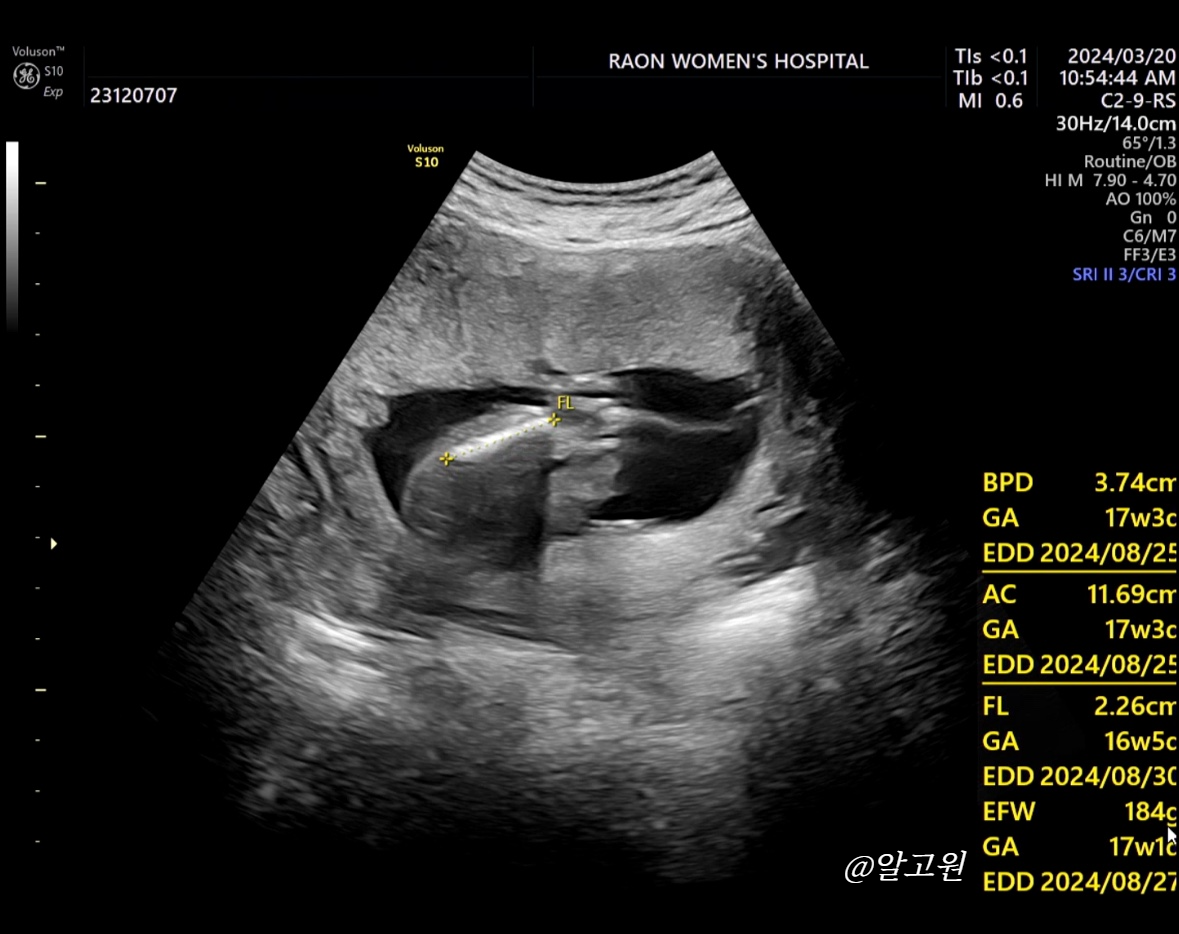

1. 아기 몸무게

- 아기 몸무게를 머리둘레, 몸통둘레(?), 다리길이로 재주시는데

저희 아가의 경우 184g 으로 나왔습니다! (16주 5일)